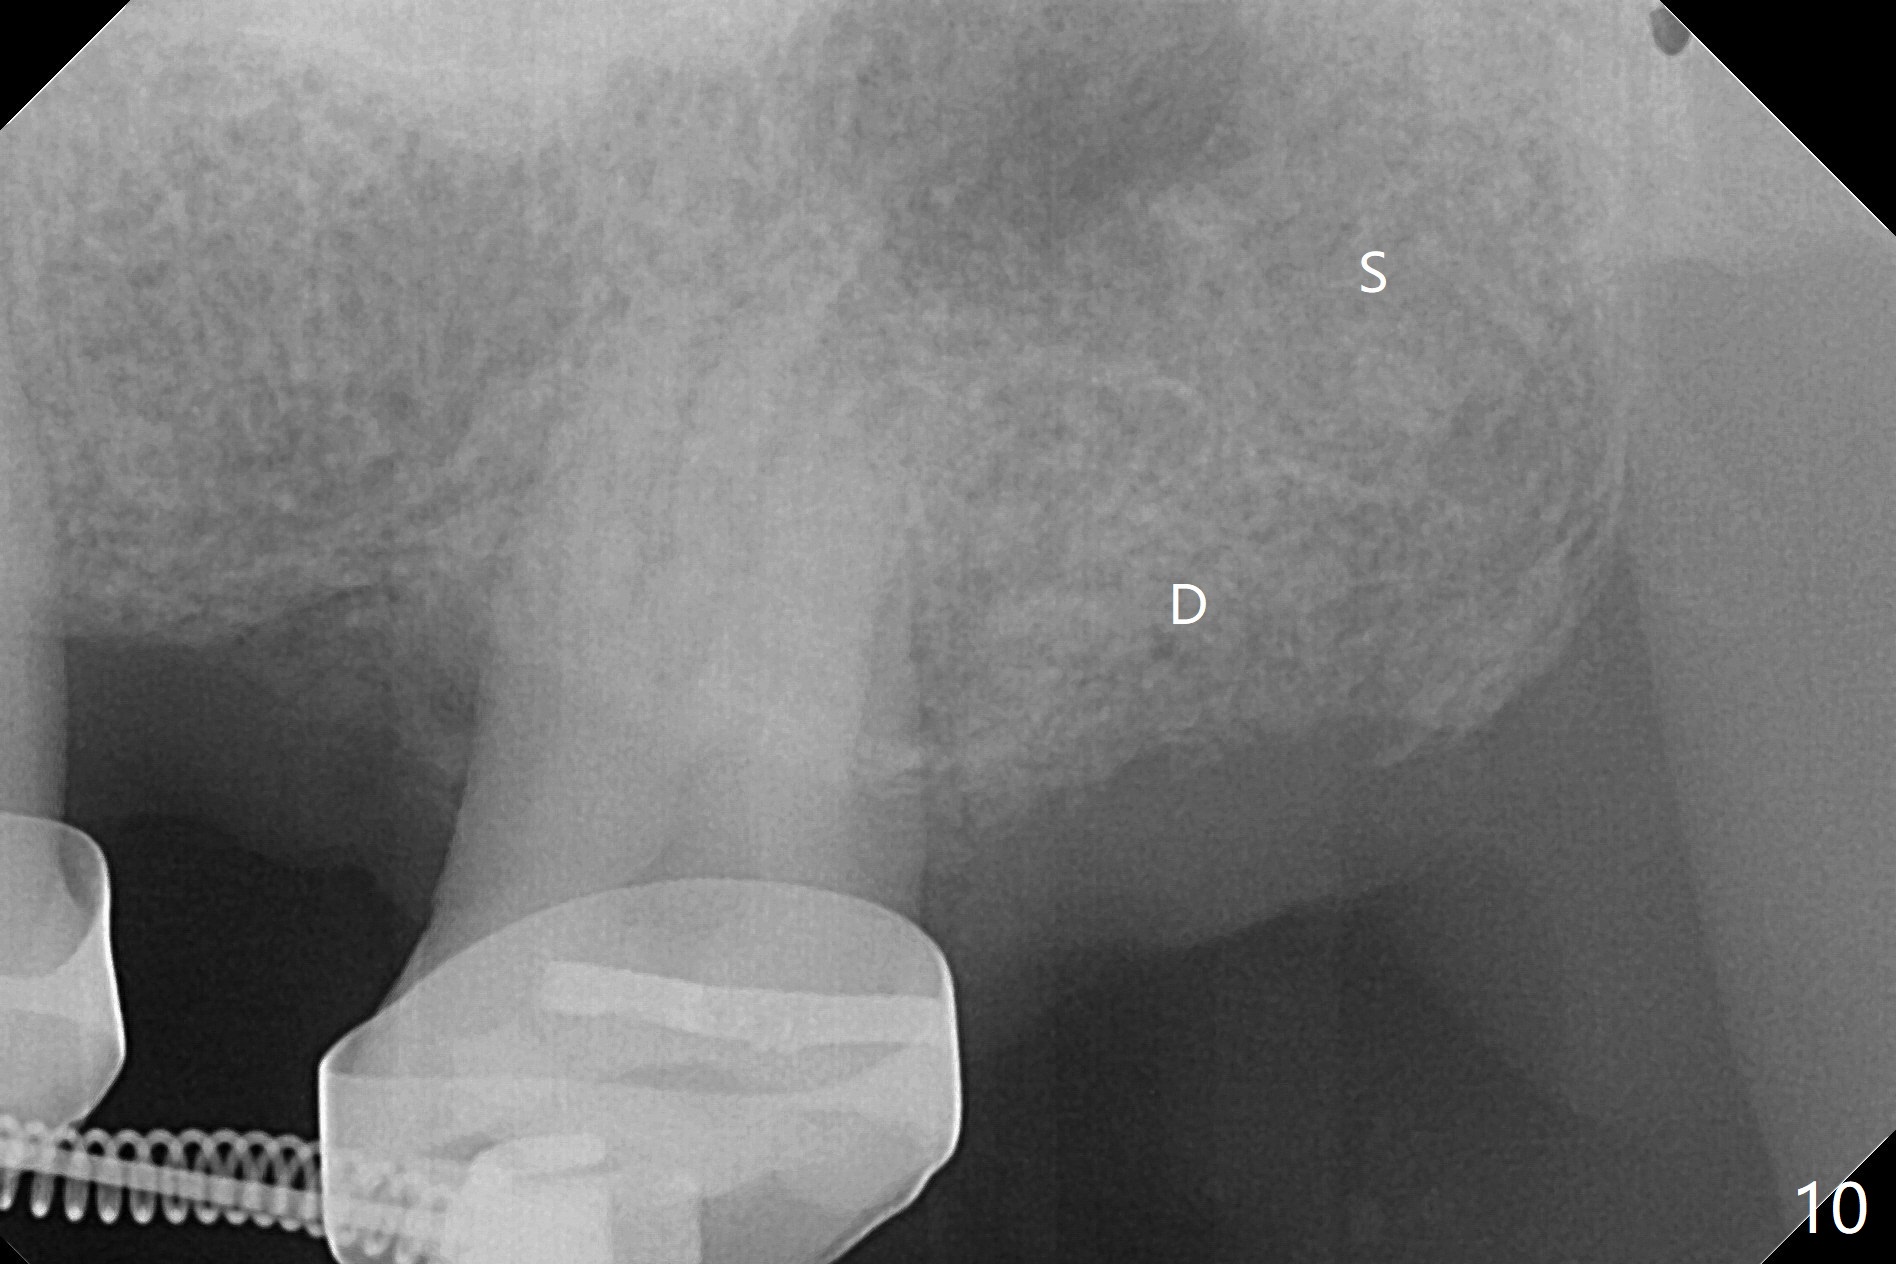

为了在左上6,左下7种植,使用右上3至左上5作为支抗推左上7远中,但是六个月效果不显著(图一),CT显示阻生牙(图一,二:8)没有阻挡。7远中植入1.6x8毫米微型植体,不过接近7根尖(图三),微型植体应该改变角度,而且往远中颊侧移位。最后效果不错(图四),植体马上启用(图五),而且同时取模做左下7导板。在微型植体牵引下,左上7的确往远中移位(图六,与图四对比),但是植体松动,马上植入3x10(2)毫米一段式植体,由于8阻挡,后者没有完全就位,稳定性差,没有启动。几天后也脱落。病人急着完成治疗,因为咀嚼困难。补救方法便是拔除阻生牙9(图七:x),让植体完全就位。切开后发现牙槽嵴处严重骨质吸收缺损(图八:D),离7很近,不适合种植。拔除8后(图九:S(socket)),两处植骨(粘性,图十),覆盖PRF膜,缝合。矫正九个月6空间相当双尖牙(图十二),还想增加2毫米才种植,病人急于完成治疗,所以再次植入微型植体,不同之处是切开,发现7远中颊侧骨质密度低(用探针),因此微型植体在腭侧植入(图十一:P),扭力似乎高,1.6x8毫米植体仿佛植入8牙槽窝(图十二:红虚线)。微型植体牵引一个月,磨牙缺牙间隙大约前磨牙大小,准备在远中(图十三)植入直径小植体(图十四),当后者整合时,用它继续推7。